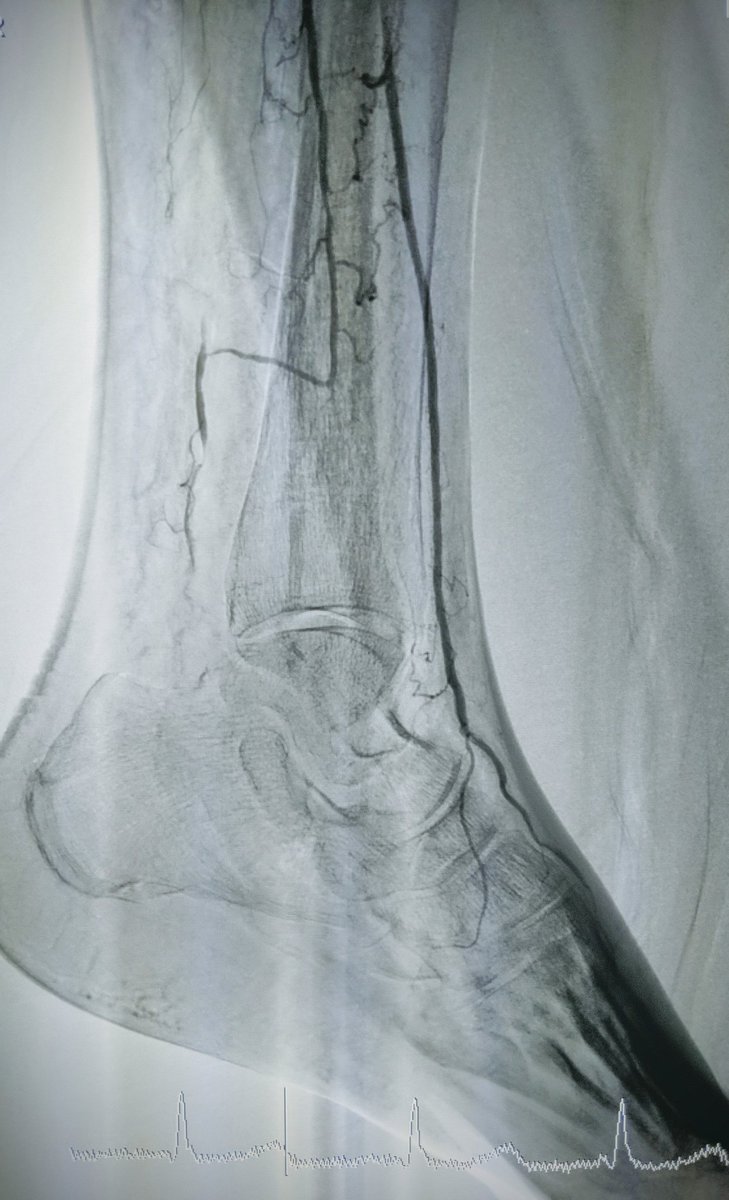

MRA can be MORE sensitive to tibial occlusive disease than DSA. MRA helped plan approach due to knowledge of hibernating AT and peroneal lumen. Successful antegrade luminal recan for #CLI #CLIfighters #mylegmylife @FadiSaab17 @Mustapja @roblookstein @DrBTKatzen @BOlivieriMD